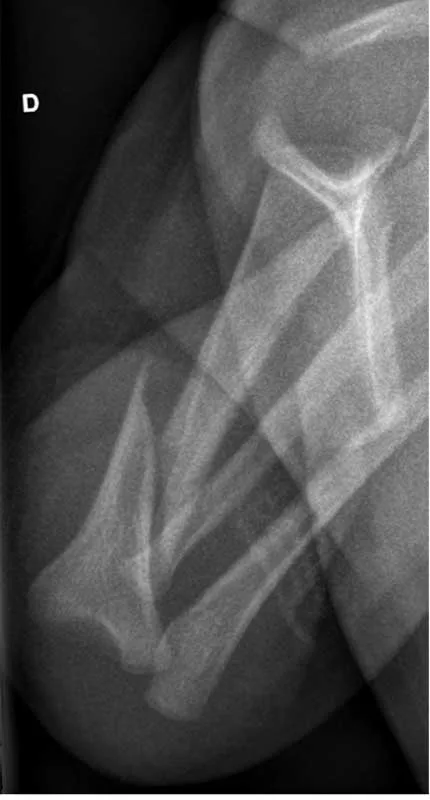

Fig. 17.3 Fracture humérale chez un enfant âgé de 8 mois. Présence d’une fracture spiroïde déplacée de l’humérus droit suspecte dans le contexte (chute des bras du père à l’anamnèse, présence par ailleurs d’une ecchymose ancienne sur la joue).